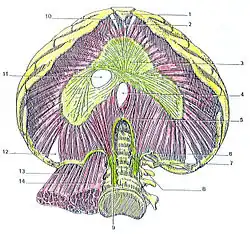

Le diaphragme est un organe propre aux mammifères[1]. Il forme une cloison musculo-aponévrotique qui sépare la cavité thoracique des cavités de l'abdomen.

Le diaphragme est un muscle digastrique organisé autour d'un centre tendineux trifolié.

Il forme une voûte à convexité supérieure constituée de deux coupoles : les coupoles diaphragmatiques droite et gauche.

Les fibres musculaires s’insèrent sur le pourtour de l'ouverture inférieure du thorax et sur les bords du centre tendineux.

Il s'organise en trois parties liées aux insertions des fibres:

- une partie sternale,

- une partie costale,

- une partie lombaire ou vertébrale.

Partie sternale

La partie sternale nait par des faisceaux très courts et grêles de la face postérieure de l'extrémité inférieure du processus xiphoïde et par quelques fibres sur la ligne blanche.

Les fibres se terminent en arrière sur la partie moyenne de la foliole antérieure du centre tendineux.

La partie sternale droite et gauche peuvent être séparé par espace médian : la fente de Marfan.

La partie sternale est limitée latéralement par le triangle sterno-costal.

Partie costale

La partie costale nait de digitations de la face interne de la paroi thoracique :

Partie lombaire

La partie lombaire ou vertébrale nait directement ou indirectement des quatre premières vertèbres lombaires.

Elle se divise en deux parties :

- une partie médiane constituée du pilier du diaphragme qui s’insère directement sur les vertèbres lombaires,

- une partie latérale qui nait du ligament arqué médial et du ligament arqué latéral.

Les tendons des deux piliers droit et gauche s'unissent pour former le ligament arqué médian formant la limite antérieure du hiatus aortique.

Les faisceaux musculaires se terminent sur les bords de l'échancrure postérieure du centre tendineux.